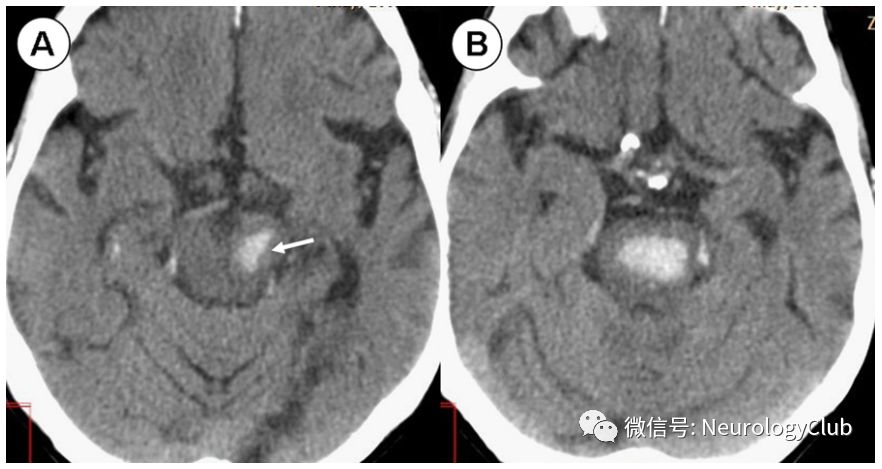

前内侧梗死(图4)导致偏瘫或半瘫、对侧共济失调、构音障碍、吞咽困难、眼球震颤,也经常出现同侧面肌麻痹。较少出现对侧本体感觉缺失,同侧眼球水平凝视麻痹及核间性眼肌麻痹。

图4:脑桥前内侧梗死;62岁患者,表现为左侧偏瘫,共济失调,构音障碍,吞咽困难,眼球震颤以及同侧水平凝视障碍;A:T2WI可见右侧脑桥轻微高信号;B-C:DWI和ADC证实急性脑桥前内侧部梗死